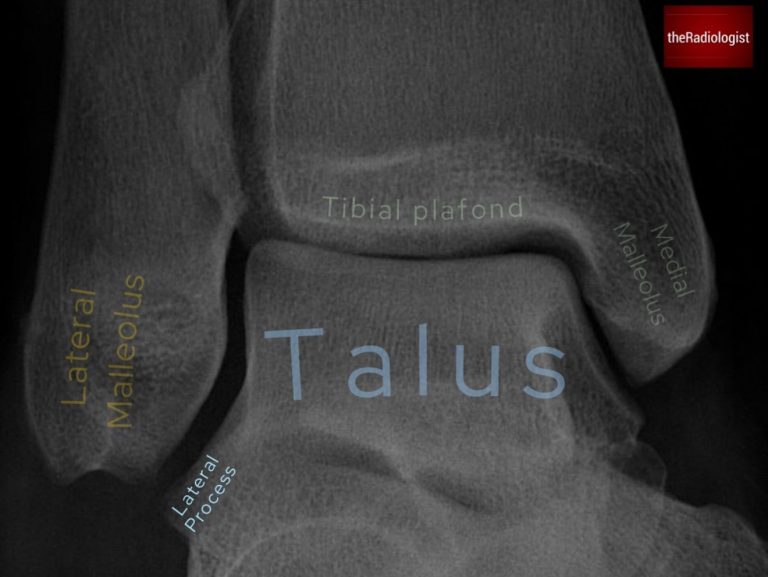

Annotated view of an mortise view ankle X-Ray.

Now trace the mortise joint: the tibial plafond with the medial and lateral malleoli and the talar dome. The joint space should be symmetric and uniform. Any asymmetry could represent a ligament injury with or without a fracture.

7. Lateral process of the talus

Pause to review the lateral process of the talus which can be subtle on X-Ray. These fractures often mimic ankle sprains and are easily missed on X-ray. If you don’t look for them, you won’t see them.

Take a moment to review the lateral process of the talus – fractures here can mimic ankle sprains.